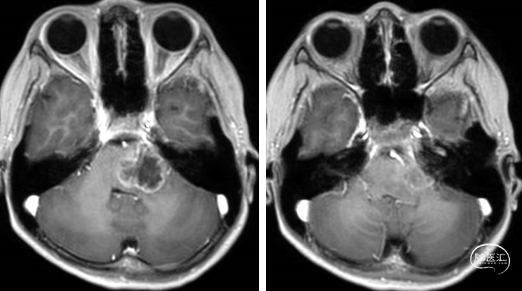

术前MRI

2023年9月13日 MRI T2

2023年9月13日 MRI+C